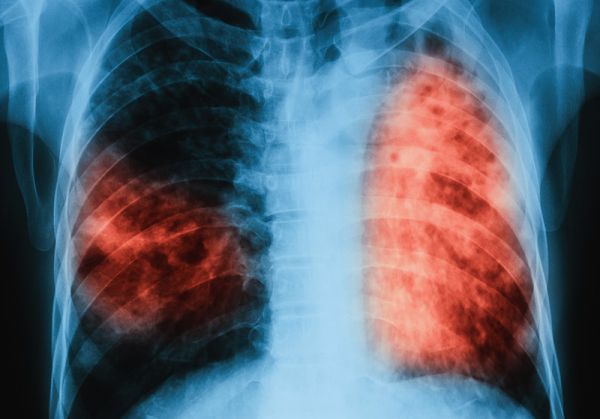

В предишния скрининг тази година – от 11 до 15 юни, се включиха 319 души от Пловдив и региона. От тях 119 са насочени за контролни прегледи, ренгтенови снимки и микробиологични изследвания на храчка. На по-голямата част – 113 човека, е направен туберкулинов кожен тест – познат като „Пробата на Манту“. С него се открива инфекция с туберкулозната бактерия. данните съобщи завеждащият отделението д-р Веселин Давчев.

След изброените изследвания е установено, че има 15 болни със съмнение за заболяването. От тях трима са диагностицирани с активна туберкулоза и са хоспитализирани, за да им се проведе активно лечение. Останалите 12 са с латентна форма на болестта и при тях вече се провежда химиопрофилактика.

Характерно за латентната туберкулоза е, че тя преминава безсимптомно и при инфектираните лица не се наблюдават клинични, микробиологични или рентгенологични данни за наличие на активно туберкулозно заболяване. Макар че хората с латентна форма на заболяването не проявяват явни симптоми на активна туберкулоза и не са носители на заразата, те могат да бъдат окачествени като постоянни резервоари на инфекцията. При някои от тях има повишен риск от развитие на активно заболяване и те могат да станат източник на инфекция, обясни д-р Давчев.

Бързото диагностициране и адекватното лечение на болните с активна туберкулоза са от първостепенно значение за осъществяване на контрол над коварното заболяване. Също така трябва да се проследи и състоянието на лицата, които са били в контакт с болния от активна туберкулоза. Ранното откриване гарантира не само излекуване на вече заразените, но и прекъсване на веригата на предаване на болестта, подчерта д-р Веселин Давчев.